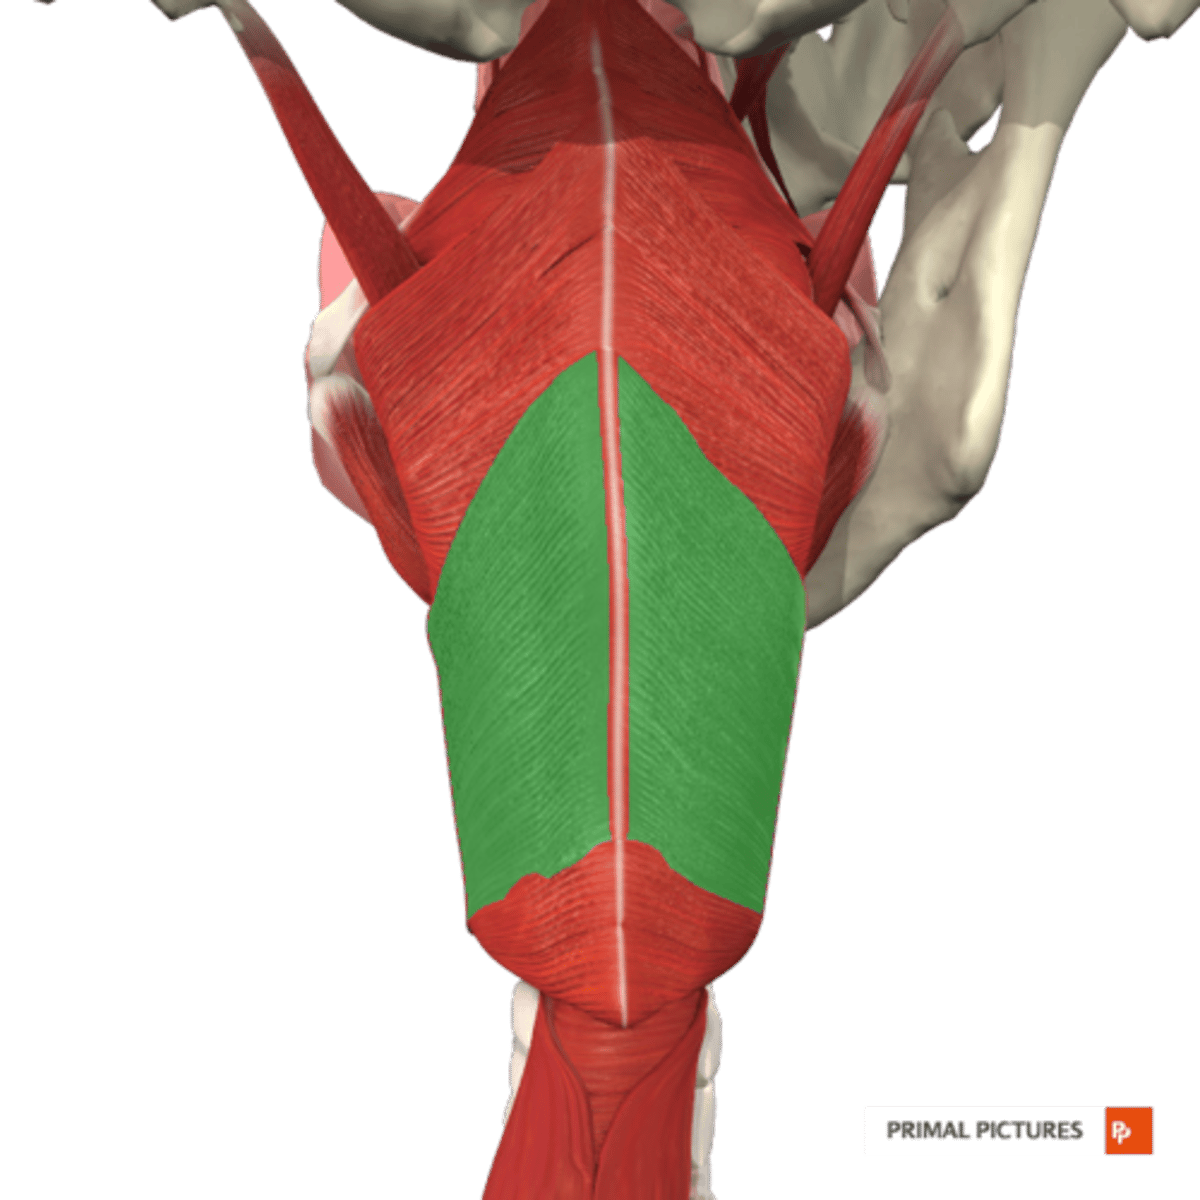

Cricopharyngeus Figure

Inferior Constrictor -

Cricopharyngeus Description

Part of Inferior constrictor

Muscular component of upper esophageal

sphincter (UES)

Origin - cricoid cartilage

Course - fans out posteriorly and medially

Insertion - midline raphe

Action - open and close upper esophageal

sphincter